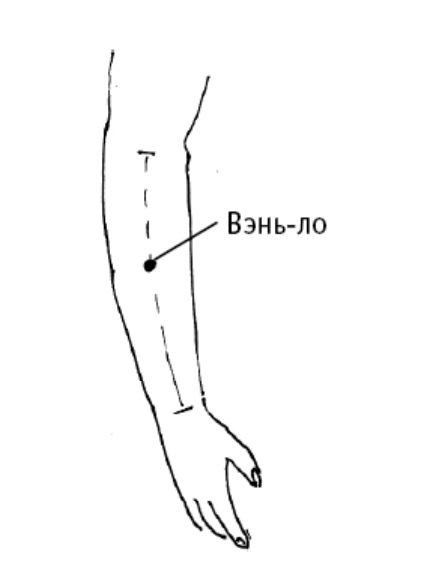

Цзянь-ши (считается успокаивающей ТОЧКОЙ ПЕРИКАРДА, наружной оболочки сердца) расположена на 3 цуня выше лучезапястной складки, сгиба запястья.

Точка используется для избавления от сердечных болезней и сердечных неврозов, для лечения сердцебиения, болей в области сердца, расстройства сна и угнетенного состояния.

Дополнительный эффект от воздействия на точку: лечение сопутствующих болезней желудочно-кишечного тракта (рвота, понос, вздутие кишечника); лечение простуды (кашель, лихорадка, боль в горле); улучшение состояния при женских болезнях (бели, аменорея или отсутствие менструации). Точку также используют для лечения локтевого сустава и других болей в руке.

Цзянь-ши (считается успокаивающей ТОЧКОЙ ПЕРИКАРДА, наружной оболочки сердца) расположена на 3 цуня выше лучезапястной складки, сгиба запястья.

Точка используется для избавления от сердечных болезней и сердечных неврозов, для лечения сердцебиения, болей в области сердца, расстройства сна и угнетенного состояния.

Дополнительный эффект от воздействия на точку: лечение сопутствующих болезней желудочно-кишечного тракта (рвота, понос, вздутие кишечника); лечение простуды (кашель, лихорадка, боль в горле); улучшение состояния при женских болезнях (бели, аменорея или отсутствие менструации). Точку также используют для лечения локтевого сустава и других болей в руке.